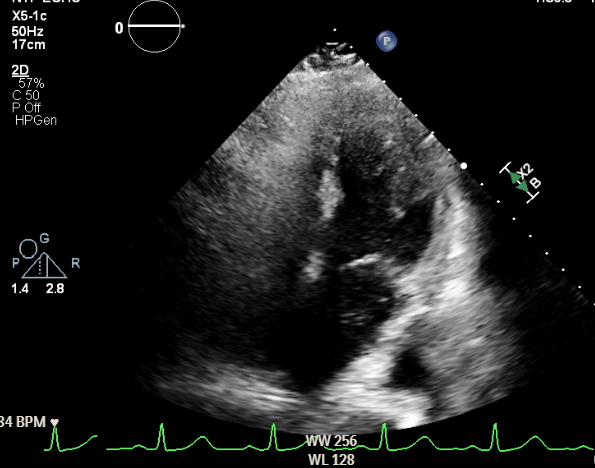

An outpatient transthoracic echocardiogram (TTE) with bubble study had shown early microbubbles in the left atrium, raising concern for an intracardiac shunt. Transesophageal echocardiography (TEE) was deferred due to esophageal varices. Repeat inpatient contrast TTE revealed a moderately dilated left ventricle but no evidence of ASD or PFO. Cardiac Magnetic resonance imaging (MRI) demonstrated a normal Qp:Qs and no anomalous venous return or intracardiac shunt. Due to persistent hypoxemia, the patient was transferred to a tertiary center. There, repeat contrast TTE showed innumerable microbubbles in the left heart after four cardiac cycles suggestive of an intrapulmonary shunt. Chest CT with contrast showed no structural evidence of an intrapulmonary shunt. Right heart catheterization confirmed a right-to-left shunt with Qp:Qs = 0.6, and microbubbles were visualized crossing from the pulmonary artery into the left atrium on intracardiac echocardiography (ICE),